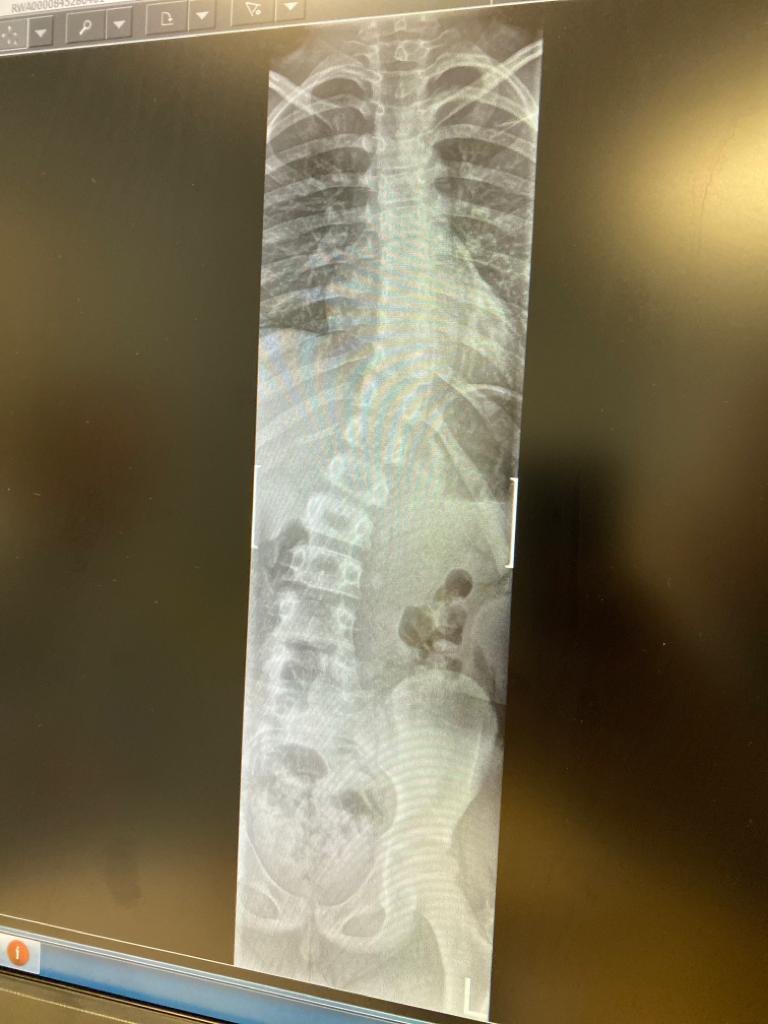

On Monday, T had an appointment with a spinal specialist. He was referred last year as his lovely OT and Physio had identified that he had a slight curve to his spine. It would appear however, that his spine is now as bendy as (now retired) Olympic medal winning UK gymnast, Beth Tweddle.

So here we are at the start of another path. And unfortunately, there is a chance that this path could end with spinal surgery. The specialists will continue to monitor the progression of the curvature, but surgery could be a real possibility in the future. Granted, not in the immediate future, but potentially somewhere along the road. And, (as is becoming an increasingly frustrating outcome) there is very little we can do to prevent it. In the words of the Dr: “If its going to happen, it will happen, and there is nothing you can do to stop it.”